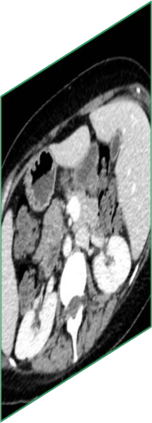

Due to the constraints of the imaging device and high cost in operation time, computer tomography (CT) scans are usually acquired with low intra-slice resolution. Improving the intra-slice resolution is beneficial to the disease diagnosis for both human experts and computer-aided systems. To this end, this paper builds a novel medical slice synthesis to increase the between-slice resolution. Considering that the ground-truth intermediate medical slices are always absent in clinical practice, we introduce the incremental cross-view mutual distillation strategy to accomplish this task in the self-supervised learning manner. Specifically, we model this problem from three different views: slice-wise interpolation from axial view and pixel-wise interpolation from coronal and sagittal views. Under this circumstance, the models learned from different views can distill valuable knowledge to guide the learning processes of each other. We can repeat this process to make the models synthesize intermediate slice data with increasing inter-slice resolution. To demonstrate the effectiveness of the proposed approach, we conduct comprehensive experiments on a large-scale CT dataset. Quantitative and qualitative comparison results show that our method outperforms state-of-the-art algorithms by clear margins.